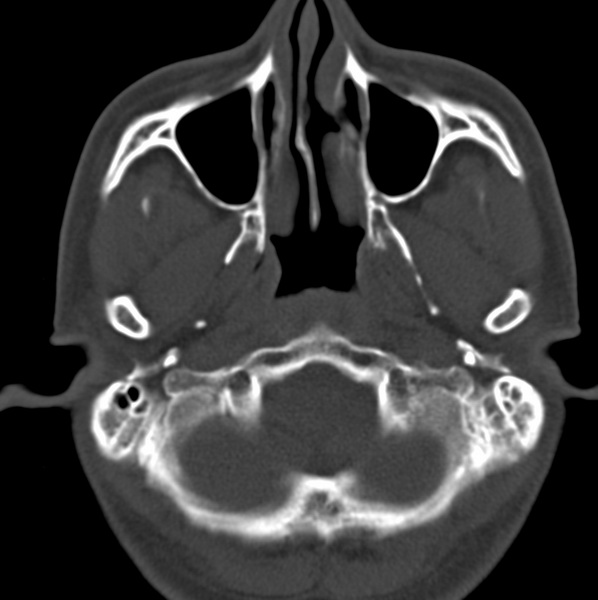

男、31、鼻咽部肿瘤放疗后请帮忙看看。

效果好,右侧破裂孔扩大,局部骨质缺损,为颅底骨质破坏。

1)鼻咽部肿瘤侵犯颅底放疗术后改变。2)左侧蝶窦炎。

咽后壁增厚,左侧咽鼓管隆突增大、咽鼓管咽口变浅,同侧咽旁间隙较窄。右侧颅底骨质破坏?为什么不在同一侧?

鼻咽部肿瘤侵犯颅底放疗术后改变.